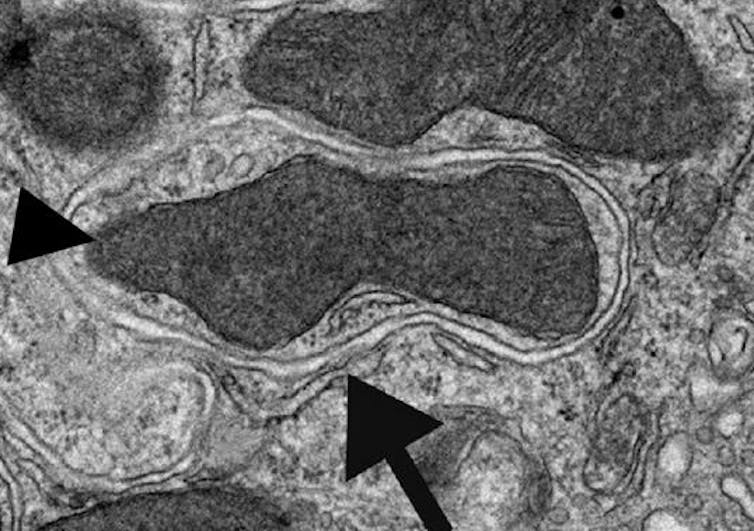

Las células de nuestro cuerpo (y cualquier célula eucariota en general, como las levaduras que hacen el pan) son capaces de envolver y atrapar dentro de membranas los orgánulos y proteínas que ya no les sirven y llevarlos al orgánulo que se encarga de degradar y reciclar (autofagia), el lisosoma.

Y lo más increíble de todo es que la célula es capaz de distinguir qué quiere degradar mediante la autofagia y qué no. Por ejemplo, en el caso de la formación de las células ganglionares de la retina (que llevan la información visual al cerebro), lo que se degrada de forma selectiva para la transformación celular son las mitocondrias, las encargadas de obtener la energía.